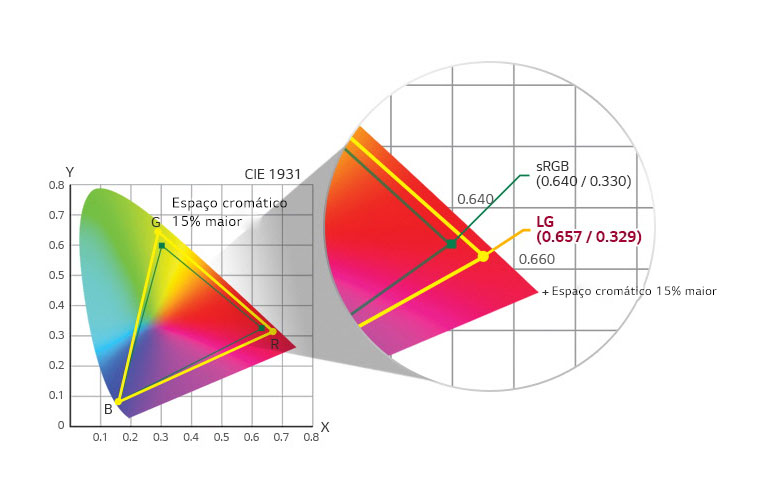

Gama de cores (Typ.)

sRGB 99% (CIE1931)